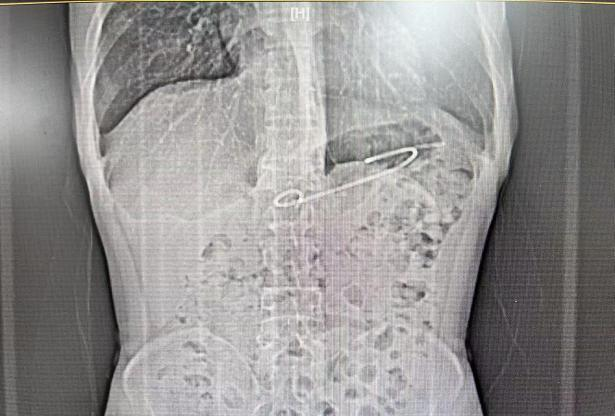

近日,51岁的王叔叔因腹痛呕吐3天入住我院消化内科,经完善相关检查后,磁共振【上腹部MRI平扫】提示:1.胰腺信号异常,多考虑:慢性胰腺炎急性发作。2.胰头颈区囊性病变,多考虑包裹性坏死。3.胰体囊性灶(囊腺瘤可能);【超声胃镜检查】提示:1.慢性胰腺炎,胰管多发结石2.胰头颈部囊性病灶(假性囊肿可能)3.浅表性胃窦炎

手术指证明确,消化内科医生团队在超声内镜引导下为患者行EUS(超声内镜)引导下胰腺假性囊肿引流术。3日后患者顺利康复出院。